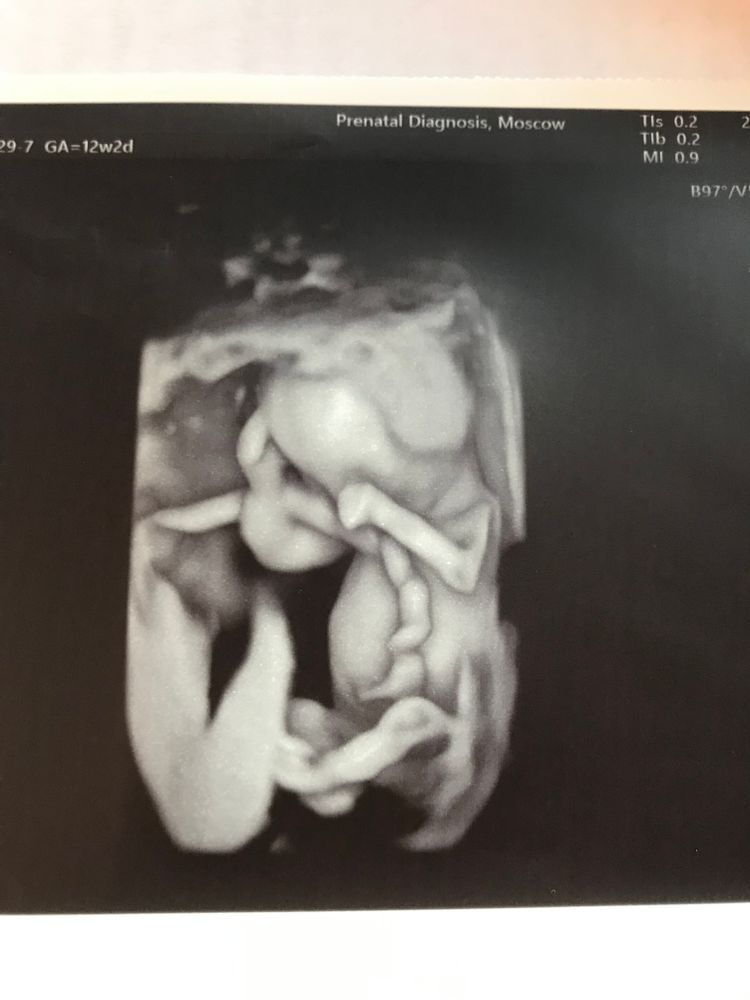

12+2 (оно же +5)

КТР 66, ЧСС 167, ТВП 1,92, нос 2,1

Плацента переползла на переднюю стенку, но пока далеко от шва. Есть маленькая ниша от рубца, но вроде не критично. Надо будет следить.

Так странно видеть человека на экране, мне казалось, что Дина на скрининге была просто инопланетянином, а тут прям человек уже 🙃